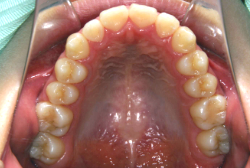

混合歯列期から治療開始した側方拡大による非抜歯症例

「配列の凸凹を治したい」という主訴で来院したケースです。診断の結果、永久歯がすべて生えそろうと、かなり厳しい叢生(歯並びの凸凹のことです)になる可能性が高いと判明しました。原因としては特に上の顎の骨が小さいため、歯を収容する容量不足になっていると診断しました。このケースの場合は、成長発育期に治療開始しますので、顎の骨を土台ごと大きくすることが可能です。

そこで、まず急速拡大装置を使用して上顎骨の拡大を行い、上顎骨の容量が拡大したことを確認後、マルチブラケット装置を使って全体の修正をする、と言う二段階の作戦をとることになりました。

この時期に使う急速拡大装置は、適切な診断に基づいて正しく使用することで確実に骨を大きくすることができます。拡大することで隙間が確保できるので、永久歯の抜歯を避けることができます。

急速拡大装置を1日1回装置の中央にある拡大ネジを、ご自身で回して頂くことで25日間くらいかけて、6mmほど拡大しました。拡大後は、上顎の前歯の隙間が広がっていることがお分かりいただけると思うのですが、土台の骨ごと広がるのでこのような隙間ができます。その後1年半くらいマルチブラケット装置を使用して、全体の修正を行いました。

結局、歯の本数を減らすことなく、すべてご自分の歯を残して正しい配列にすることができました。このケースの場合、2009年10月より拡大と経過観察を行い、2012年3月より1年2ヶ月マルチブラケット装置を装着、2013年5月に治療を終了しました。2段階で行う治療としては短期間で終了しているケースと思います。